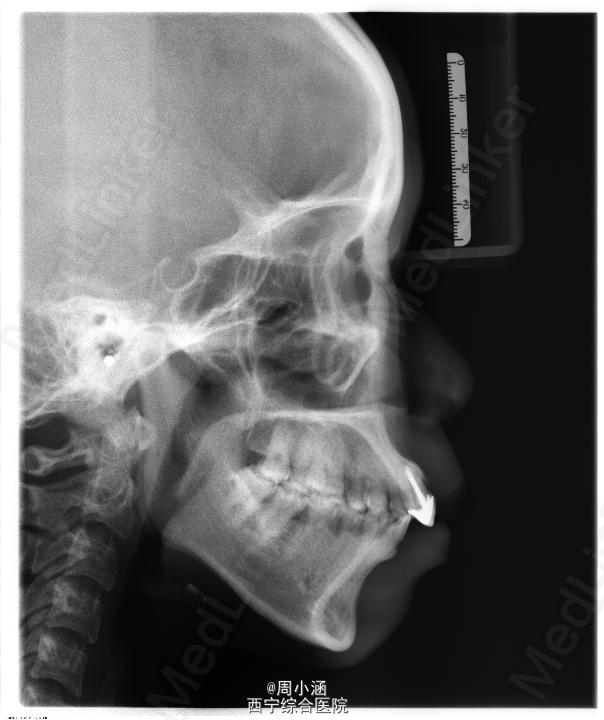

青年女患者,双颌前突十余年,自诉无明显诱因出现双颌前突十余年,逐渐加重,影响美观及前牙咬合

双侧颌面部基本对称,侧面观:面下1/3较突,呈凸面型。双侧颞下颌关节区无压痛弹响,髁突动度基本正常,开口型↓,开口度3.5cm。口内检查:前牙深覆合覆盖,牙列整齐,17、18及47、48锁合,11、21不良修复体,15残冠,口腔卫生欠佳。双颌前突,SNA 97.2°,SNB 87.8°,ANB 9.4°

双颌前突,上下颌前牙区根尖下截骨后退术+双侧上颌骨部分切除术+双侧下颌骨去骨皮质术+坚固内固定术+15,24,34,44拔除术